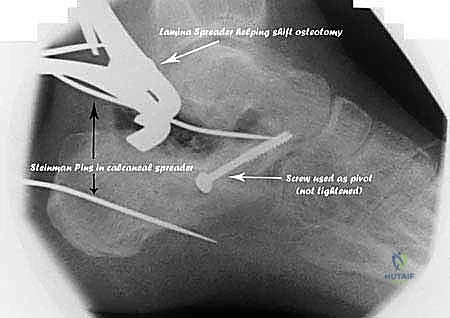

الخلاصة الطبية السريعة: يُعد تصحيح سوء التئام عظم العقب (Calcaneal Malunion) وتثبيت المفصل تحت الكاحل (Subtalar Arthrodesis) من أعقد الإجراءات الجراحية في طب جراحة العظام، وهو إجراء حيوي وجذري لعلاج آلام الكعب المزمنة، والتشوهات الميكانيكية، والتهابات المفاصل الناتجة عن كسور الكعب التي لم تلتئم بالشكل التشريحي الصحيح. يتضمن هذا الإجراء الدقيق إعادة تشكيل الهيكل العظمي المتضرر (Osteotomy)، استعادة ارتفاع وتوازن القدم، وتثبيت المفصل تحت الكاحل لضمان استعادة وظيفة القدم الطبيعية وتخفيف الألم بشكل نهائي. تتطلب هذه الجراحة مهارة استثنائية، وهو ما يقدمه الأستاذ الدكتور محمد هطيف، أستاذ جراحة العظام والمفاصل بجامعة صنعاء، بخبرته التي تتجاوز العقدين في أعقد جراحات القدم والكاحل.

3. التصوير المقطعي المحوسب (CT Scan) مع إعادة البناء ثلاثي الأبعاد (3D Reconstruction)

لا يمكن التخطيط لجراحة تصحيح سوء التئام عظم العقب بدون أشعة مقطعية. توفر الأشعة المقطعية رؤية دقيقة للتشريح العظمي المشوه، وتحدد بدقة مكان الانحشار الشظوي، حالة الأسطح المفصلية، ومسار الأوتار. التخطيط ثلاثي الأبعاد يسمح للجراح ببناء نموذج افتراضي للقدم وتحديد أماكن القطع العظمي المطلوبة بدقة مليمترية قبل الدخول إلى غرفة العمليات.